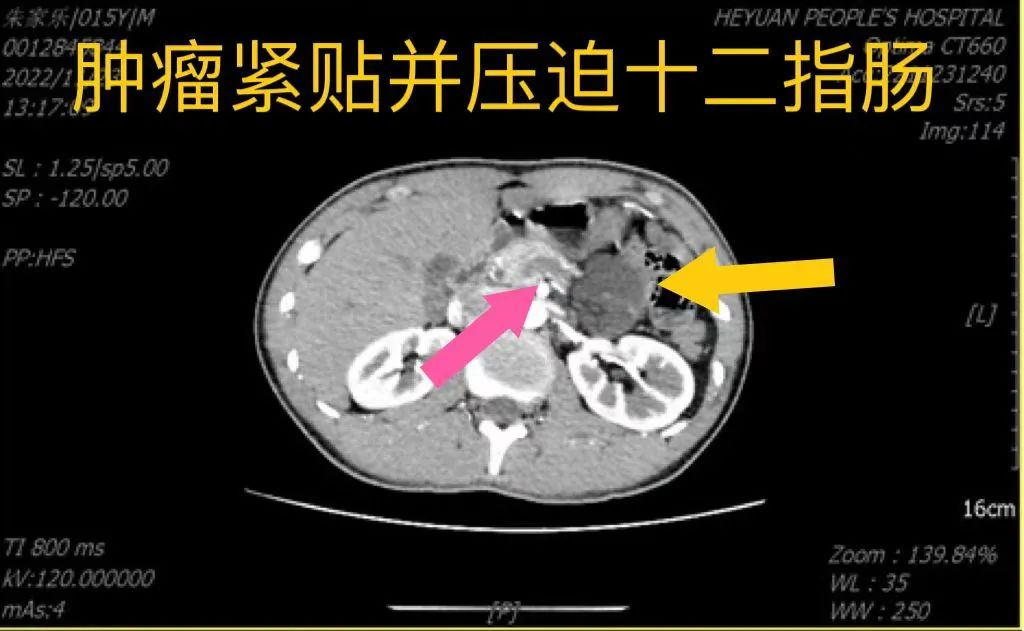

患者朱某是一名15岁中学生,因腹部胀痛不适5天来院就诊,行腹部增强CT及增强MRI扫描提示腹膜后淋巴管瘤,大小约100×85×36mm。肿瘤起自胰腺钩突,行程中半包绕腹主动脉、肠系膜上动脉,与左肾静脉关系密切,紧贴并压迫十二指肠水平部,终止于上段空肠。(图1-3)

图3:肿瘤紧贴并压迫十二指肠